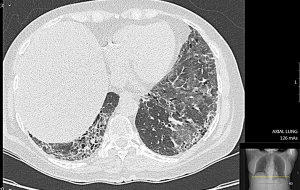

בשלבים המוקדמים הסתמנות של ILD אינה ספציפית ולרוב סמויה. כשליש מהחולים מתלוננים על שיעול יבש, ממושך וטורדני וקשיי נשימה במאמץ, מיחושים לא ספציפיים בחזה, חולשה ועייפות. עם התקדמות השינויים הפיברוטיים בריאות, מופיע חוסר אוויר במאמץ קטן ובמנוחה. לרוב החולים יש. בבדיקה פיזיקלית שומעים חרחורים יבשים מעל בסיסי הריאות. בשלבים המתקדמים של ה-Fibrosis בריאות וירידה בריווי החמצן בדם, מופיעים סימנים של אי ספיקת לב ימין (גודש ורידי צוואר, הפרעות קצב הלב, הגדלת כבד, מיימת ובצקות ברגליים. בדיקת בית החזה בעזרת צילומי רנטגן איננה רגישה לגילוי של ILD; הבדיקה המומלצת לגילוי ולהערכה של ILD היא בדיקת טומוגרפיה ממוחשבת ברזולוציה גבוהה של בית החזה (High Resolution Computer Tomography ,HRCT). בדיקת HRCT מאפשרת לקטלג שינוים אינטרסטיציאליים בשדות ריאות כמו "זכוכית מט" (Ground Glass Opacities, GGO), שינוים רשתיים (Reticular Changes) או שינוים בצורת "חלת דבש" (Honey Combing), והרחבה של הסמפונות ((Traction Bronchiectasis. לשינויים אינטרסטיציאליים בריאות מספר צורות; בהכשר ל-CTD השכיחות ביניהן NSIP (Non-Specific Interstitial Pneumonia) ו-UIP (Usual Interstitial Pneumonia). ב-Scleroderma, יותר שכיחה NSIP ופחות שכיחה צורה של UIP; ל-UIP התקדמות ה-Fibrosis עמוקה יותר לעומת NSIP. קיימת התאמה בין חומרת השינויים ב-HRCT וירידה במדדי תפקודי נשימה; פגיעה ביותר מ-20 אחוזים משטחי הריאות, המודגמת ב-HRCT, מנבאת שיעורי תחלואה ותמותה גבוהים יותר בקרב חולי Scleroderma. הומלץ על ביצוע HRCT של בית החזה לכל חולה Scleroderma חדש ומעקב סדיר אחרי שינויים בפרקי זמן נדרשים (בין 6–12 חודשים), בייחוד בחולה עם גורמי סיכון לILD) Scleroderma נרחבת, הימצאות נוגדנים 70-SCL). הפרעה בתפקודי נשימה נמצאה בכ-25 אחוזים מהחולים כבר ב-3 השנים הראשונות מתחילת ה-Scleroderma. בין המדדים העיקריים להערכת מצב הריאות בחולי Scleroderma בדיקת נפח FVC (Forced Vital Capacity) ובדיקת חילופי גזים DLCO (Diffusing Capacity of the Lungs For Carbon Monoxide). ירידה מקבילה ב-FVC ו-DLCO מצביעה על קיומה של ILD. ערכי DLCO ו-FVC נחשבים ירודים כאשר הם מתחת ל-80 אחוזים מהתקן ביחס לגיל, מין וגובה. ירידה מעבר ל-50 אחוזים מצביעה על פגיעה ראייתית קשה ומנבאת שיעור תמותה גבוה ב-3 השנים הבאות. ירידה של כ-10 אחוזים ב-FVC וכ-15 אחוזים בDLCO בפרקי זמן קצרים נחשבת כסמן למחלת ILD מתקדמת. חולי Scleroderma עם ILD מתקשים בהליכה של 6 דקות (Minute Walk Test 6); מרחק הליכה הנמוך מ-300 מטר וירידה בריווי חמצן הנמדדת באצבע בעזרת מכשיר Oxymeter לפני ואחרי המאמץ מעיד על מעורבות ריאות משמעותית. לבדיקת שטיפת סמפונות אין תרומה משמעותית לאבחנה של ILD, לרוב נעזרים בה בחשד למחלת ריאות אחרת (זיהום וכדומה). ביופסיה פתוחה מריאה איננה חובה בחשד ל-ILD; לרוב ביופסיה מתבצעת לצורכי מחקר או במקרים בהם אבחנה של ILD מוטלת בספק.

ב-Scleroderma מחלת ריאות אינטרסטיציאלית מופיעה בשנים הראשונות מתחילת Scleroderma, בעיקר ב-Scleroderma נרחבת והמצאות נוגדנים SCL-70. התסמינים הקליניים של ILD אינם ספציפיים ויכולים להיות מוסתרים על ידי ביטוים של Scleroderma. ישנה חשיבות רבה לגילוי מוקדם של ILD ולהערכה קלינית מסודר כולל מעקב אחרי שינוים ב-HRCT תפקודי נשימה. טיפול מוקדם עשוי למנוע את התפשטות של Fibrosis בריאות, לשמור על תפקודי הנשימה ולמנוע הידרדרות נשימתית ולבבית. בין הטיפולים המומלצים Cyclophosphamide או Mycophenolate Mofetil בהתחשבות בביטוים אחרים של Scleroderma (עור, מפרקים, שרירים, לב). המקום של טיפולים ביולוגיים ו-HSCT לטיפול ב-ILD בחולי Scleroderma טרם הובהר. טיפול ב-Nintedanib מאט קצב הידרדרות של תפקודי נשימה ומונע התפשטות של Fibrosis בריאות.